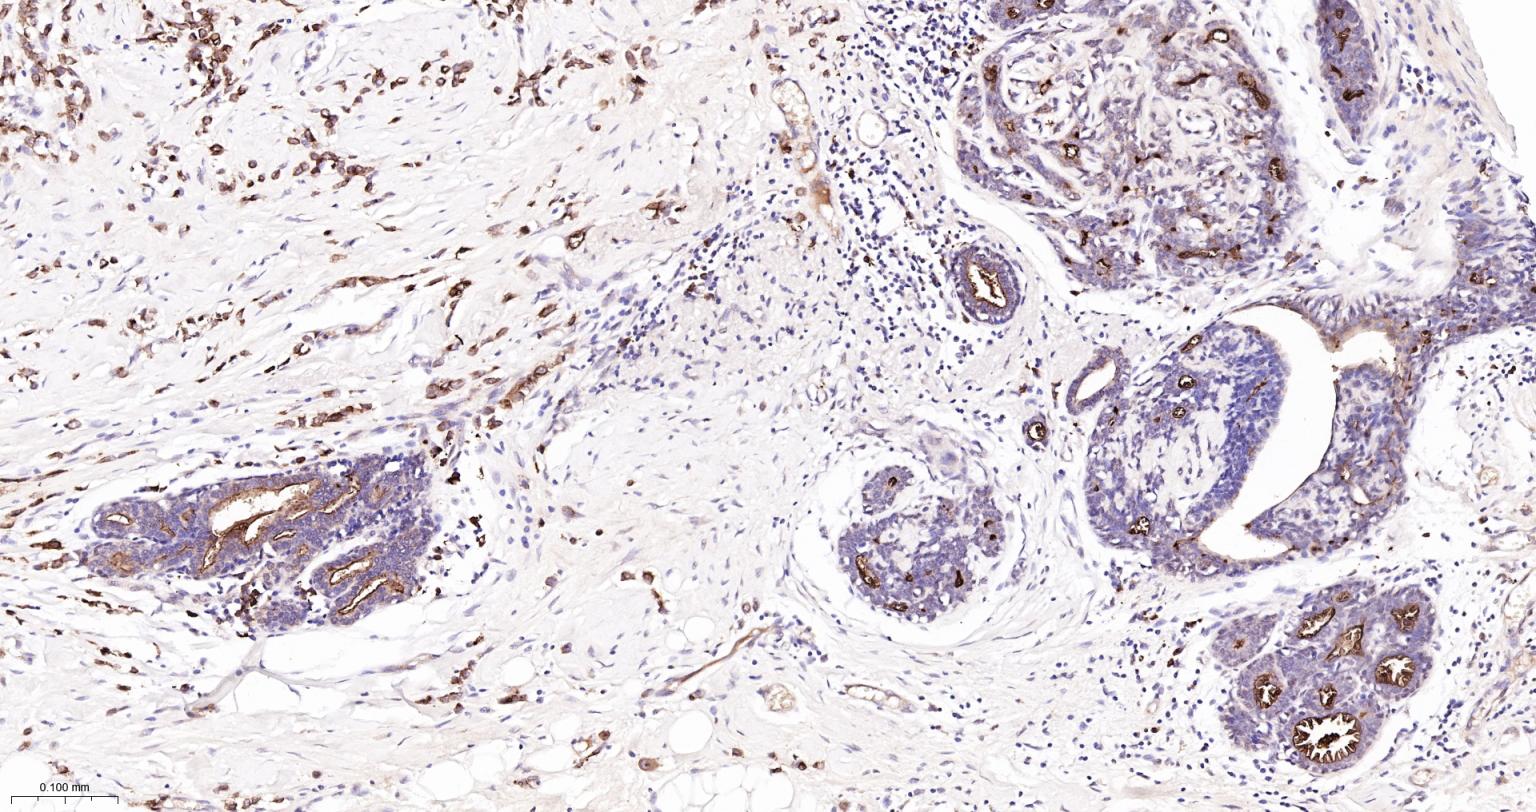

Paraformaldehyde-fixed, paraffin embedded Human Endometrial Cancer; Antigen retrieval by boiling in sodium citrate buffer (pH6.0) for 15 min; Antibody incubation with MUC1 Monoclonal Antibody, Unconjugated(bsm-52576R) at 1:200 overnight at 4°C, followed by conjugation to the bs-0295G-HRP and DAB (C-0010) staining.